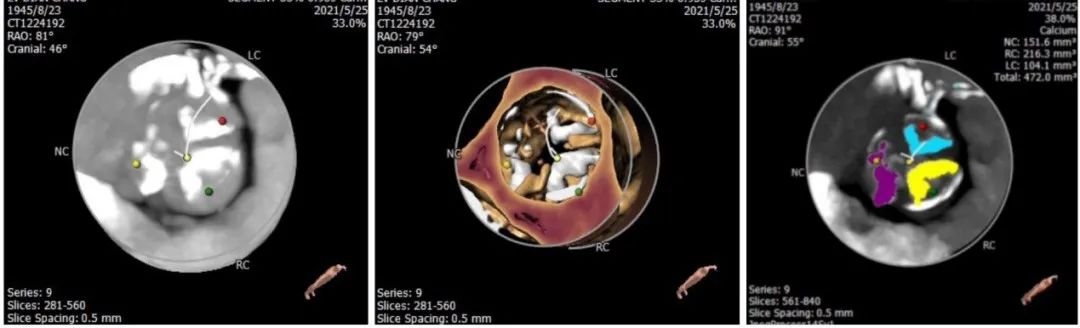

主动脉根部评估:

CT数据显示该患者为三叶三窦式主动脉瓣。

1. 主动脉瓣瓣环周长70.6mm,平均周长径 22.5mm,SOV:28.5mm*28.7mm*29.9mm,瓣叶增厚,瓣上钙化明显。

2. 左冠开口高度14.3mm,右冠开口高度16.4mm,高度可,根据瓦氏窦内径和瓣叶长度综合判断,冠脉堵塞风险小,双侧冠脉钙化严重。

钙化评估:

中度钙化,HU850积分472m㎡,RCC钙化最严重,其次为LCC、NCC。

心室情况:

左室前后径28.7mm,左室最小径13.6mm,瓣环下6mm存在心肌膨出,